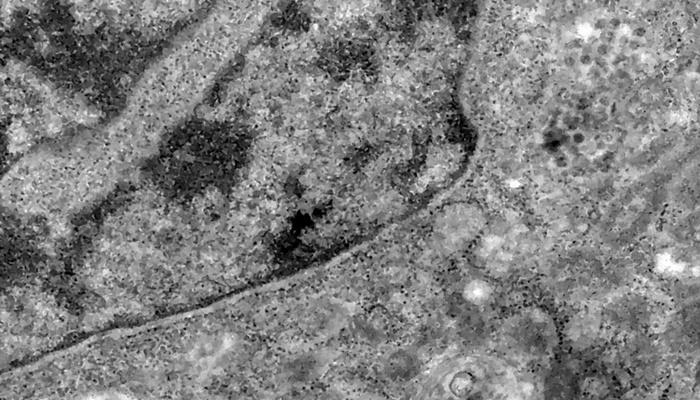

Pesquisadores brasileiros conseguiram, pela primeira vez, detectar a presença do coronavírus em retinas. O estudo pode contribuir para compreender melhor a dinâmica do vírus e as sequelas em pacientes infectados.

Os pesquisadores analisaram retinas de pacientes que morreram em decorrência da covid-19 e compararam com fotos dos olhos desses pacientes quando vivos para analisar as diferenças e formas de aferir a presença do vírus a partir da retina.

Segundo o professor da UFRJ e um dos coordenadores do estudo Rubens Belfort Jr, a retina é um biomarcador importante, pois faz parte do sistema nervoso, mas é mais acessível, permitindo identificar a presença do vírus em determinados locais do corpo, como nesse sistema.

Além de identificar a presença do vírus e de reservatórios dele nos corpos dos pacientes, o professor explica que os resultados do estudo podem auxiliar no processo de entendimento e enfrentamento das sequelas de pessoas que contraíram a covid-19.

“A pesquisa pode ajudar a entender a existência das sequelas e como combater às sequelas, como aquelas relacionadas alterações neurológicas que alguns pacientes com covid-19 desenvolvem”, disse Rubens Belfort.

As informações obtidas pela pesquisa podem contribuir para a compreensão das causas das sequelas. “Será que desenvolve porque é alteração imunológico ou tem relação com o vírus que ficou?”, indaga, exemplificando que tipo de questões carecem de melhores explicações. (Com Agência Brasil)